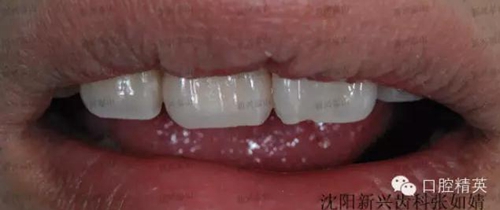

看看最后的成果吧。

真實的蛻變----熱牙膠根管充填之后的牙冠修復(fù)

怎么樣,真的是一次真實的蛻變吧!

牙齒在制作時花了點(diǎn)心思,既關(guān)閉了前牙縫隙,又沒有使這顆牙變得很大,患者非常滿意,很高興。